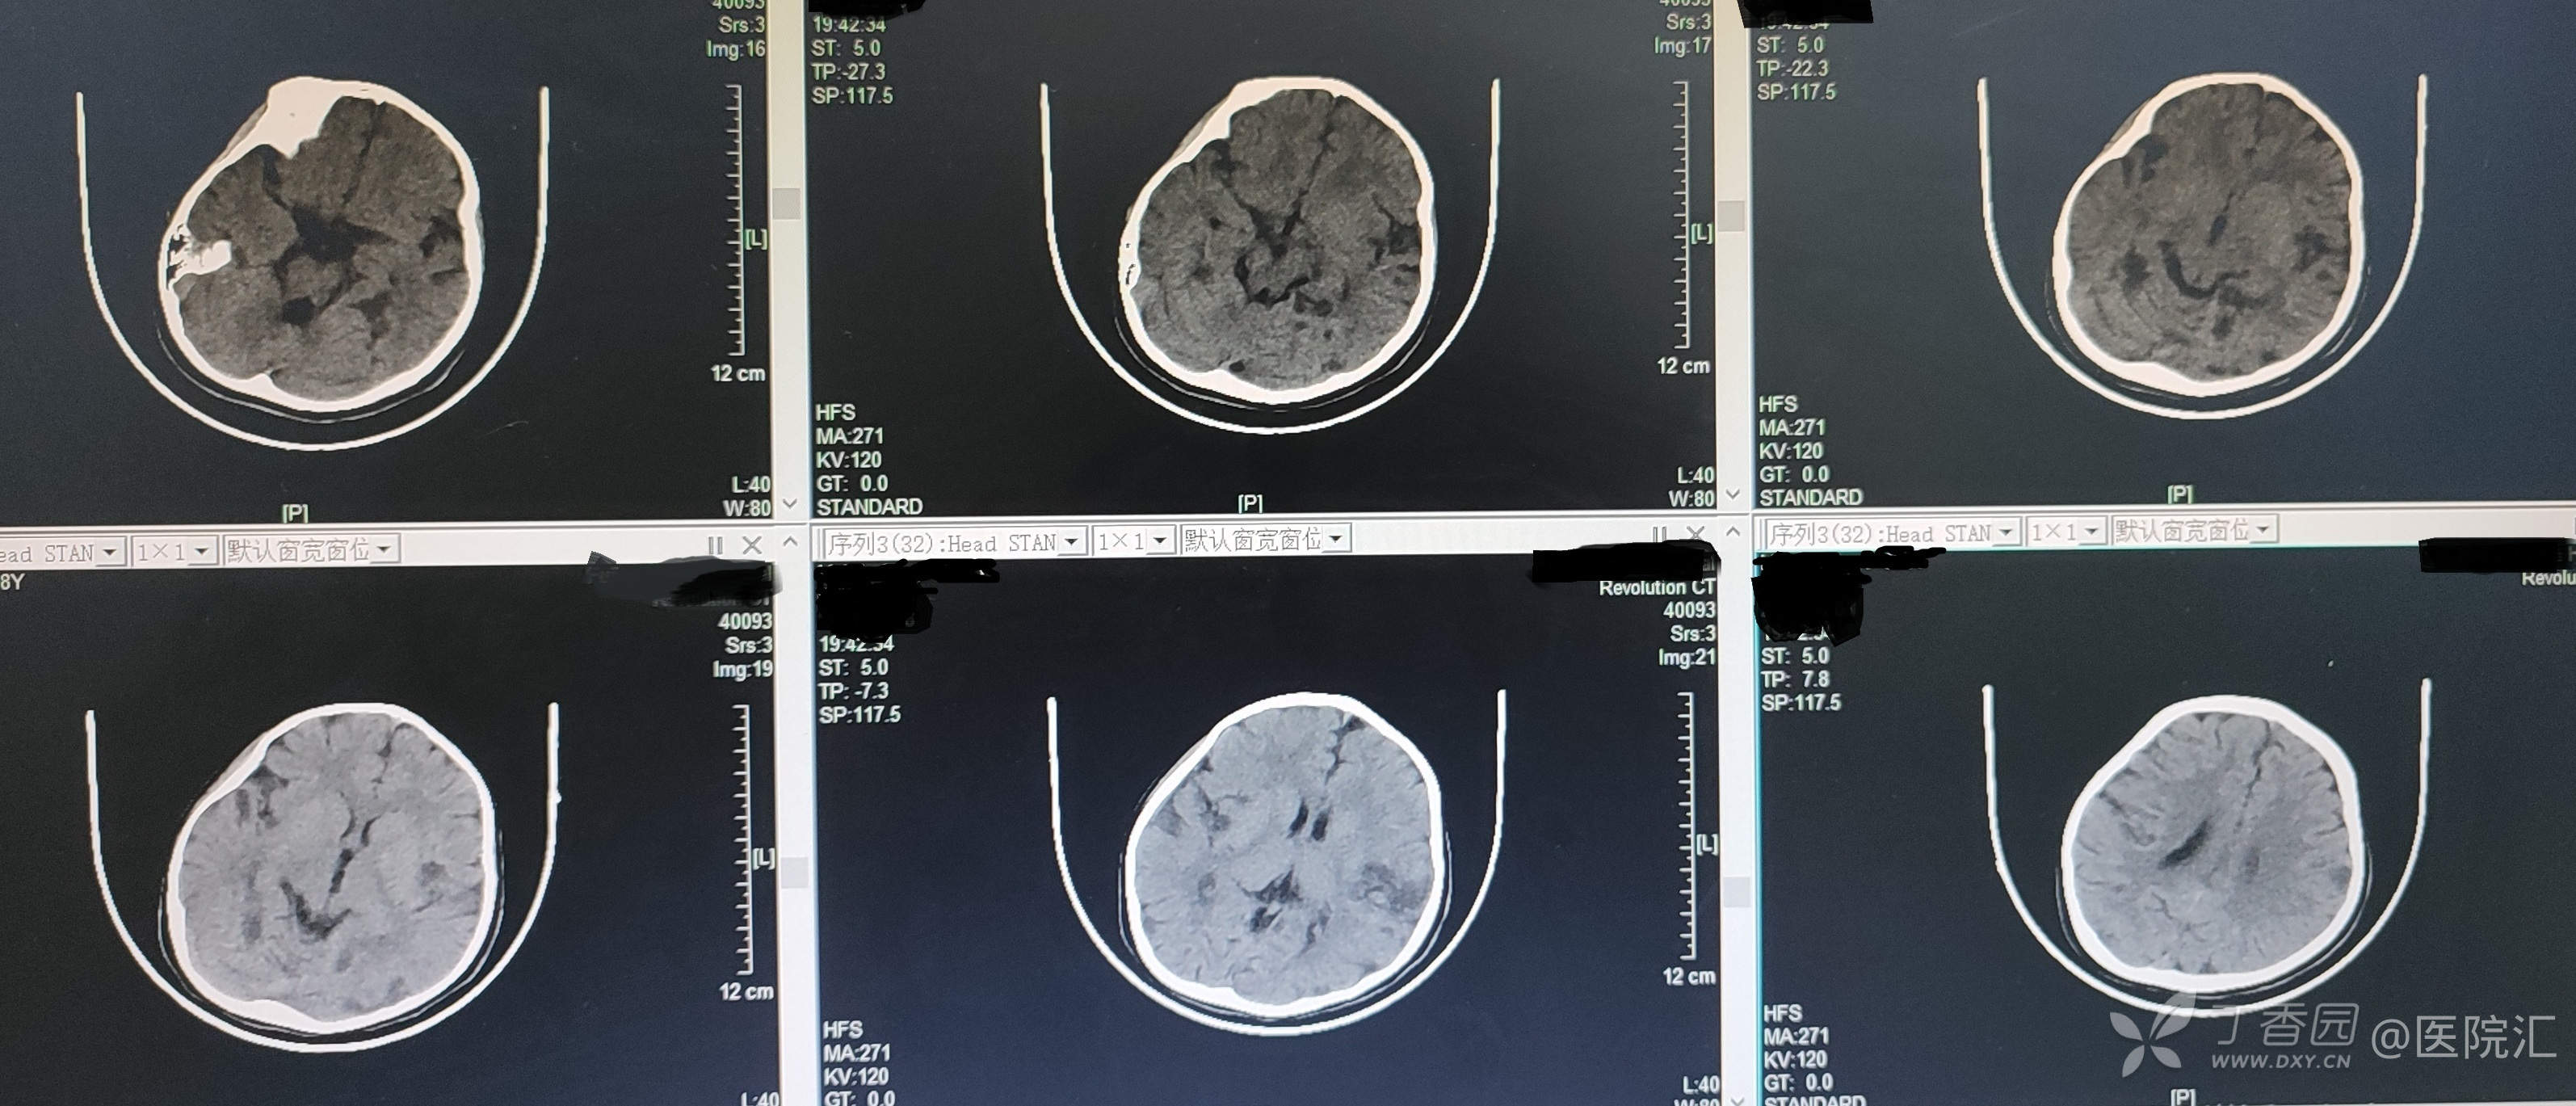

急诊查血常规:WBC 25.37×109/L,N 21.9×109/L,HB 128g/L,PLT 412×109/L;血生化:LDH 486IU/L,HCO3 10mmol/L;肌钙蛋白I 0.147μg/L;凝血功能正常;头颅CT示双侧颞顶枕叶脑实质内多发斑片状低密度灶。

图1 患儿头颅CT表现